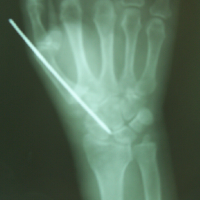

Case:5 RollTendon Arthroplasty

Arthroscopy Surgeon in Ahmedabad|Limb Reconstruction Doctor

Pre-Op

Arthroscopy Surgeon in Ahmedabad|Spine Treatment In Jaipur

Post-Op